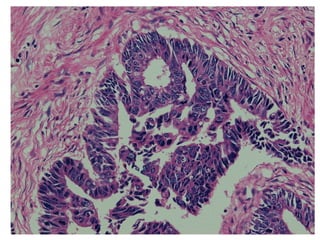

Ung thư biểu mô tuyến phế

quản

1. Nhu mô phổi bị thay thế bởi các cấu trúc nhú hay tuyến.

2. Các nhú phân nhánh phức tạp, có trục liên kết rõ. Tế bào bao phủ

quanh nhú loại trụ, kích thước không đều, nhân lớn, mất cực tính,

ưa kiềm, chất nhiễm sắc thô.

3. Các tuyến có kích thước không đều, méo mó hoặc không rõ hình

tuyến. Các tế bào tuyến mất cực tính, có vùng nhiều hàng. nhân

lớn, mất cực tính, ưa kiềm, chất nhiễm sắc thô.

4. Mô đệm tăng sinh xơ, có xâm nhập tế bào viêm một nhân.

Các nhú phân nhánh phức tạp, có trục liên kết rõ. Tế bào bao phủ

quanh nhú loại trụ, kích thước không đều, nhân lớn, mất cực tính, ưa

kiềm, chất nhiễm sắc thô.

Các nhú phân nhánh phức tạp, nhân tế bào u không đều, mất cực tính, ưa

kiềm

Các tuyến ung thư nằm trong mô đệm xơ hóa

Tính bất thường của tế bào u